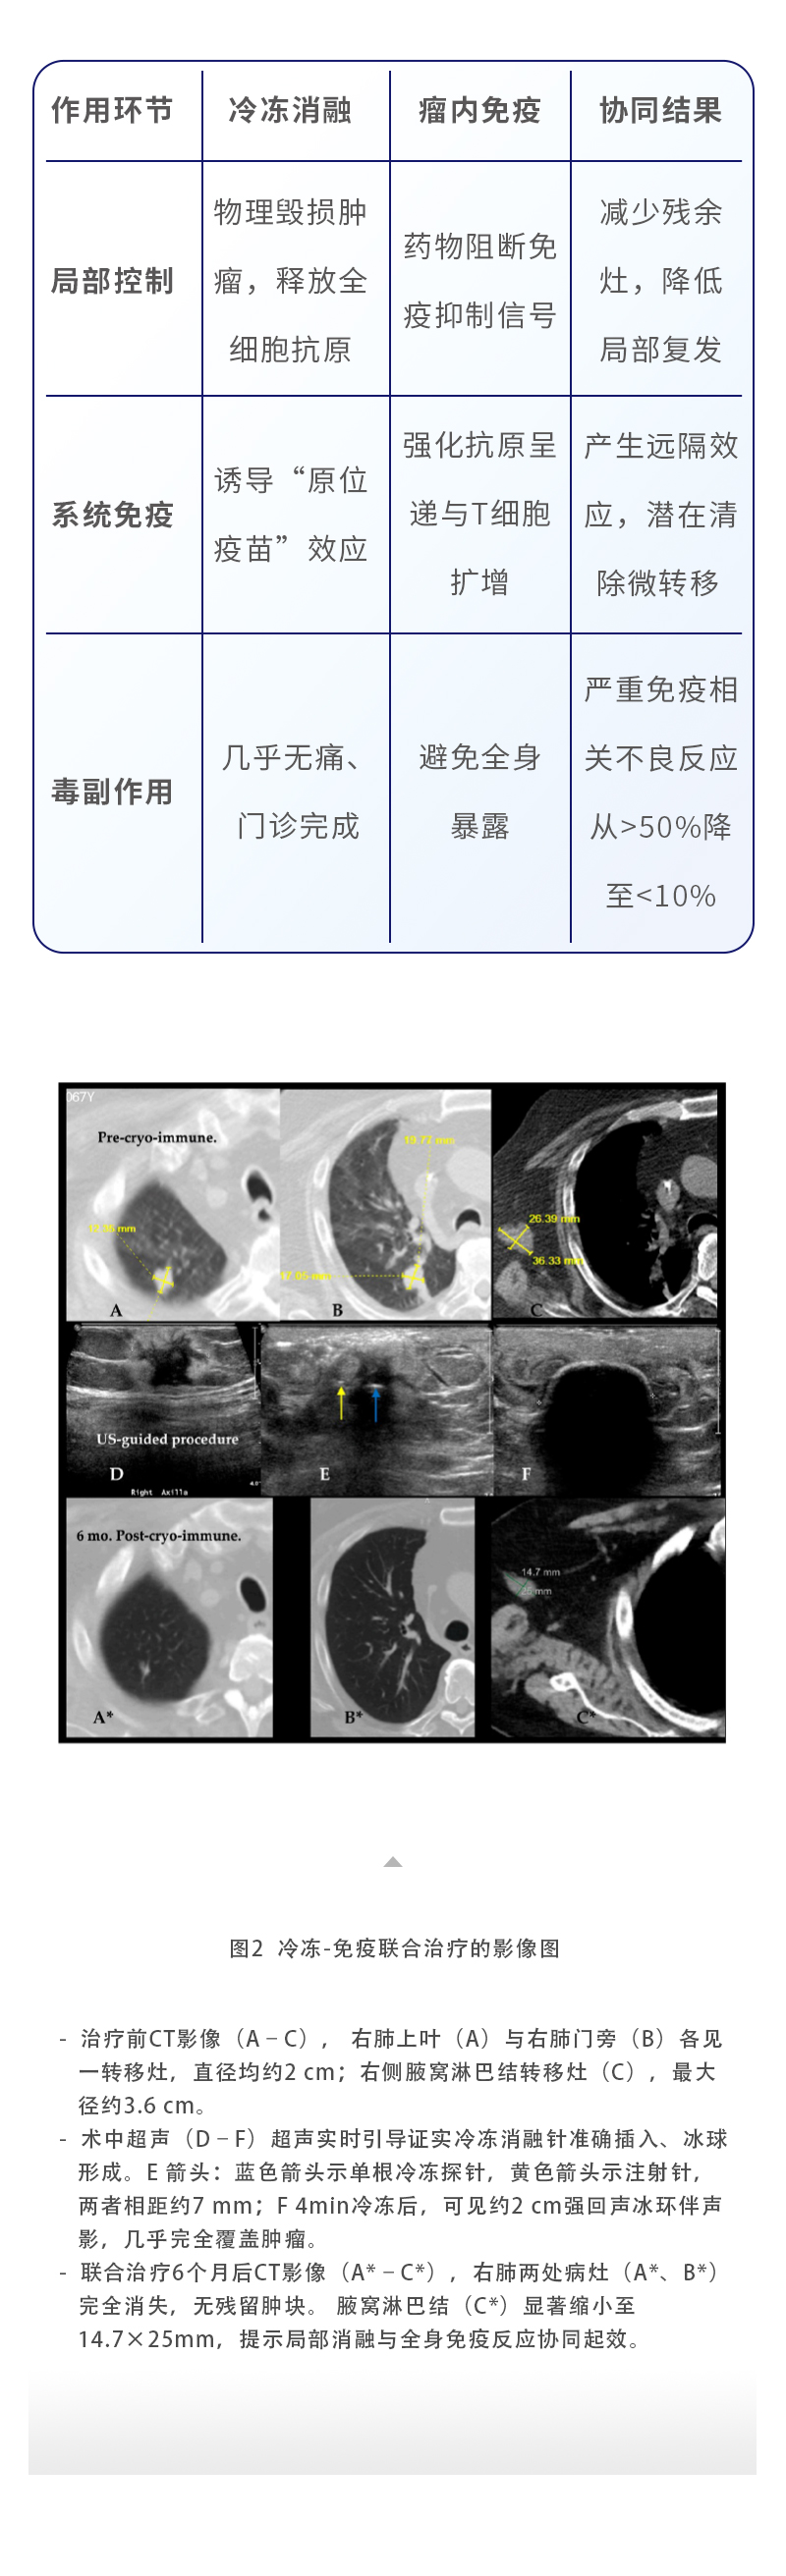

【HYGEA·科研資訊】冷凍消融聯(lián)合免疫治療